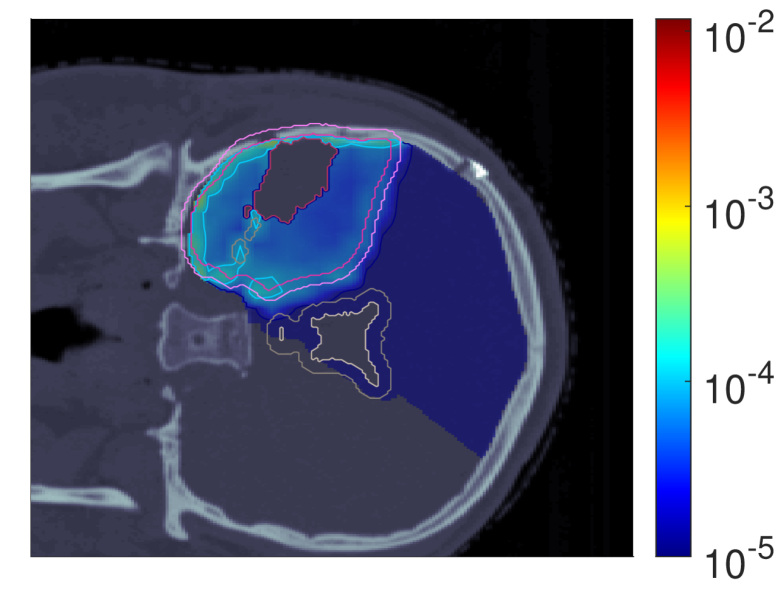

Figure 2 shows the optimal slice images of the dose (left), dose-averaged LET (middle) and POLO distribution (right). On the underlying CT scan, the tumor volumes are marked by violet to purple contours, while the VS (ventricles and 4 mm4\text{\,}\mathrm{mm} fringe) is outlined in white and gray. We observe the high-dose region covering all of the GTV, with a largely homogeneous transition to the clinical and planning target volumes (CTV, PTV), and a moderate to severe overlap to the VS. The dose-averaged LET distributes in layers, with increased values around the contour edge of CTV/PTV and local peaks at the distal ends of the proton beams. Accordingly, hot spots on the POLO map are found in regions where dose and dose-averaged LET scale up, or close to the VS. Beyond the PTV, the POLO map reveals cold spots, due to the steepness of the dose and dose-averaged LET gradients.

dRBE,fxd_{RBE,fx}ABCD ldl_{d}ABCD ppABCD

Refer to caption Refer to caption Refer to caption

NTCP:45.59 %NTCP:$45.59\text{\,}\mathrm{\char 37\relax}$ABCD

Figure 2: Optimal 2D slice images of the RBE-weighted fractional dose dRBE,fxd_{RBE,fx}, the dose-averaged linear energy transfer ldl_{d} and the probability function values pip_{i} for the baseline plan. The dose distribution (left) shows high target coverage with decreasing exposure beyond the CTV/PTV margins, but also visibly overlaps with parts of the VS. Meanwhile, for the dose-averaged LET (middle), layered homogeneity in the target volumes and local maxima at the distal ends of the proton beams can be observed. This results in more pronounced levels of POLO values within the target volumes, particularly in the presence of local dose-averaged LET maxima and in the environment of the VS. Referring back to the POLO model from Equation 1 and (3), we can expect exactly this type of coherence between the model output, the physical input feature profiles and the increased local risk near the VS. The baseline treatment plan exhibits a complication risk of 45.59 %45.59\text{\,}\mathrm{\char 37\relax} after evaluation of the POLO distribution with NTCPpNTCP_{p}.